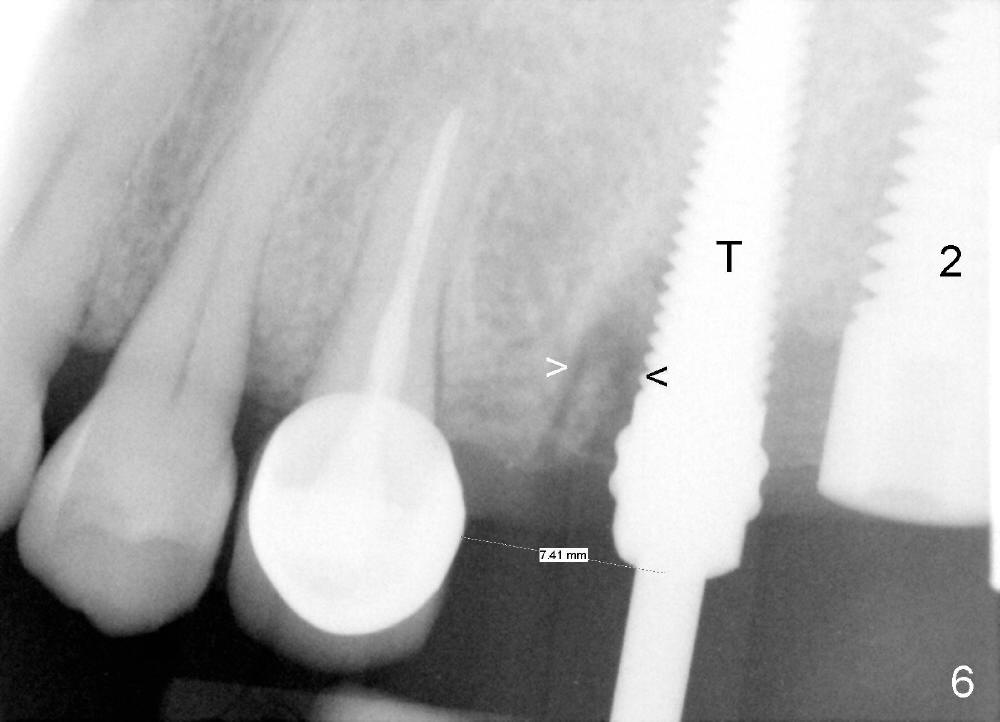

In fact, the implant at the 1st molar is planned to be placed 5.5 mm from the distal surface of the 2nd premolar (Fig.5). When the 1st intraop PA is taken with a 4.5x20 mm tap (Fig.6: T), the deviation is not noted (Fig.6: 7.5 mm vs. 5.5 mm in Fig.5). The trajectory of the implant (5x20 mm) remains deviated (Fig.7).

The trajectory should be corrected as early as possible and by changing the direction (Fig.8: from black line to red one). It should be not so difficult because of soft bone in the posterior maxilla and the mesiobuccal socket space (Fig.6 between arrowheads). It should be not too late to change the trajectory of an implant just placed.